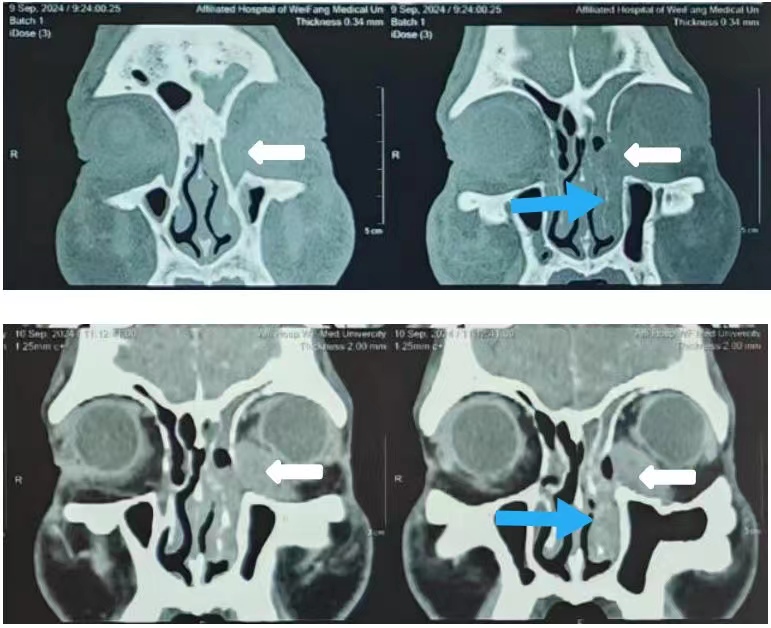

患者女,62岁,因左眼内眦肿胀1年于2024年8月19日入院。体格检查:左眼内眦部下方隆起,扪及直径约1.6 cm×1.8 cm的包块,质硬,轻微压痛,肿物自泪囊窝处向眶内延续。泪道冲洗:右眼上下泪小管内冲水通畅。左眼下泪小管冲水少量入咽,大部原路返流;上泪小管冲水全部原路反流,不能探入泪囊。眼眶彩色多普勒超声(彩超)检查(图1):左眼泪囊区可见低回声区,范围约2.4 cm×2.2 cm×1.8 cm,边界清,内回声欠均匀。彩色多普勒血流显像(color doppler flow imaging, CDFI):内可见树枝样较丰富血流信号。眼眶计算机断层扫描(computed tomography, CT)检查(图2):1)左侧泪囊鼻泪管及下鼻道内异常密度影,考虑肿瘤性病变可能大;2)左侧骨性鼻泪管增宽。眼眶磁共振成像(magnetic resonance imaging, MRI)检查(图3)示左侧泪囊鼻泪管及下鼻道内异常信号,考虑肿瘤性病变可能大。实验室检查结果未见明显异常。于2024年8月20日在全身麻醉下经皮肤切口联合鼻内镜入路行左眼眶泪道肿物切除术,先自内眦部肿物表面皮肤做切口,见肿物有完整致密薄膜,呈灰白色,向泪囊窝内延续;转至鼻内镜下,自泪颌缝前约6~7 mm纵向切开鼻黏膜向下切至下鼻甲黏膜,向后剥离鼻黏膜,暴露上颌骨额突及下鼻甲,使用咬骨钳及动力磨钻去除骨性鼻泪管内侧壁,见泪囊、鼻泪管膨大,将泪囊、鼻泪管连同鼻泪管口附近部分下鼻甲、下鼻道黏膜充分游离,其间见鼻泪管受挤压后鼻泪管口有不规则的灰白色软性颗粒样物质溢出;经内眦切口将肿物摘除。将鼻黏膜复位覆盖创面,可降解止血棉填塞固定鼻黏膜,分层缝合内眦切口。标本巨检:病变累及泪囊、鼻泪管全长,大小约为3.5 cm×2.5 cm×1.6 cm,外壁呈灰白色,有较厚的包膜结构,局部切开可见内含大量白色质软胶冻状的不规则颗粒样、乳头样结构;病理诊断(图4):(左眼泪囊部)上皮源性肿瘤,囊性结构,衬覆柱状上皮、鳞状样上皮,伴有乳头状结构,可见少量黏液细胞。CK7(部分+)、CK5/6(+)、S-100(少量+)、P63(+)、SOX10(少量+)、Ki-67阳性细胞数约2%、PAS染色(少量+)。结合组织学形态及免疫组化结果,符合泪囊导管囊性扩张伴鳞状细胞化生,伴乳头状瘤形成,伴少量黏液细胞化生。患者术后3周时复诊见鼻黏膜基本愈合,出院后曾到耳鼻喉科会诊建议观察随诊;2024年11月2日第二次复诊见左侧鼻腔黏膜愈合好,未见复发改变(图5),患者除溢泪症状,无其他不适。下一步诊疗计划:定期复诊,术后6个月以上无复发可考虑行使用鼻黏膜再造泪道的结膜-鼻腔吻合置管术。

图 2 一例泪道乳头状瘤的眼眶CT结果

Figure 2 Orbital CT results of a case of lacrimal papilloma

左侧泪囊鼻泪管内异常密度影(白箭头);左侧骨性鼻泪管增宽(蓝箭头)。Abnormal density shadow in the left lacrimal sac and nasolacrimal duct (white arrow); Widening of the left bony nasolacrimal duct(blue arrow).

患者男,61岁,因左眼溢泪2个月于2024年9月16日入院。CT检查结果:1)左眼眶内肌锥外肿物,明显强化,考虑恶性肿瘤可能;2)双侧上颌窦炎、筛窦炎;3)左侧骨性鼻泪管扩张。查体:左内眦部下方隆起,扪及硬结,范围约2 cm×3 cm,边界不清,自泪囊区向眶内延续(图6)。泪道冲洗:经左眼上下泪小管冲洗全部对点反流。彩超检查结果:左眼泪囊显示不清,左眼眶内下方可见低回声区,范围约0.6 cm×0.5 cm×1.3 cm,边界不清,内回声不均匀,CDFI:内可见丰富血流信号(图7)。于2024年9月17日在全身麻醉下经皮肤切口联合鼻内镜入路行左眼眶泪道肿物切除术,术中见肿物无明显包膜,呈暗红色,质韧,与周围组织轻度粘连,周围临近软组织质韧;肿物向下附于内眦下方眶骨表面、与眶骨膜不易分离,向泪囊窝及眶内延续,与下斜肌起点处粘连,未累及内直肌、下直肌,将下斜肌起点附近骨膜连同肿物一起切除;鼻内镜下操作,见骨性鼻泪管骨质明显吸收,内壁可见鼻泪管暴露,去除骨性鼻泪管内侧壁、下鼻甲前端,见泪囊、鼻泪管膨大,易于剥离,将泪囊、鼻泪管及骨膜连同鼻泪管口附近部分鼻黏膜充分游离,经内眦切口将肿物摘除。标本巨检:泪囊鼻泪管膨大,呈暗红色,鼻泪管末端包含喇叭口样结构的下鼻甲下鼻道黏膜,大小约为4 cm×2 cm×2 cm。病理检查:(左眼眶肿物)恶性肿瘤,鼻泪管颞侧切缘未见恶性肿瘤;鼻泪管鼻侧切缘及泪囊部鼻侧切缘查见恶性肿瘤(图8)。免疫组化:CK(+)、CK5/6(+)、P40(+)、NUT(+)、P53(野生型)、Ki-67(+,50%)、CD56(局灶+)、CgA(-)、Syn(局灶+)、CD99(-)。诊断:(左眼眶肿物)低分化癌,结合形态及免疫组化,符合鼻窦NUT癌。确诊后嘱患者至综合医院肿瘤科进一步检查、治疗。患者回当地医院肿瘤科接受了化学治疗(具体方案不详),未再复诊。

图 6 一例泪道癌眼眶CT结果

Figure 6 Orbital CT results of a case of lacrimal carcinoma

左眼眶内肌锥外肿物(白色箭头);左侧骨性鼻泪管扩张(蓝色箭头)。Extraconal mass in the left orbit(white arrow); Dilatation of the left bony nasolacrimal duct(blue arrow).